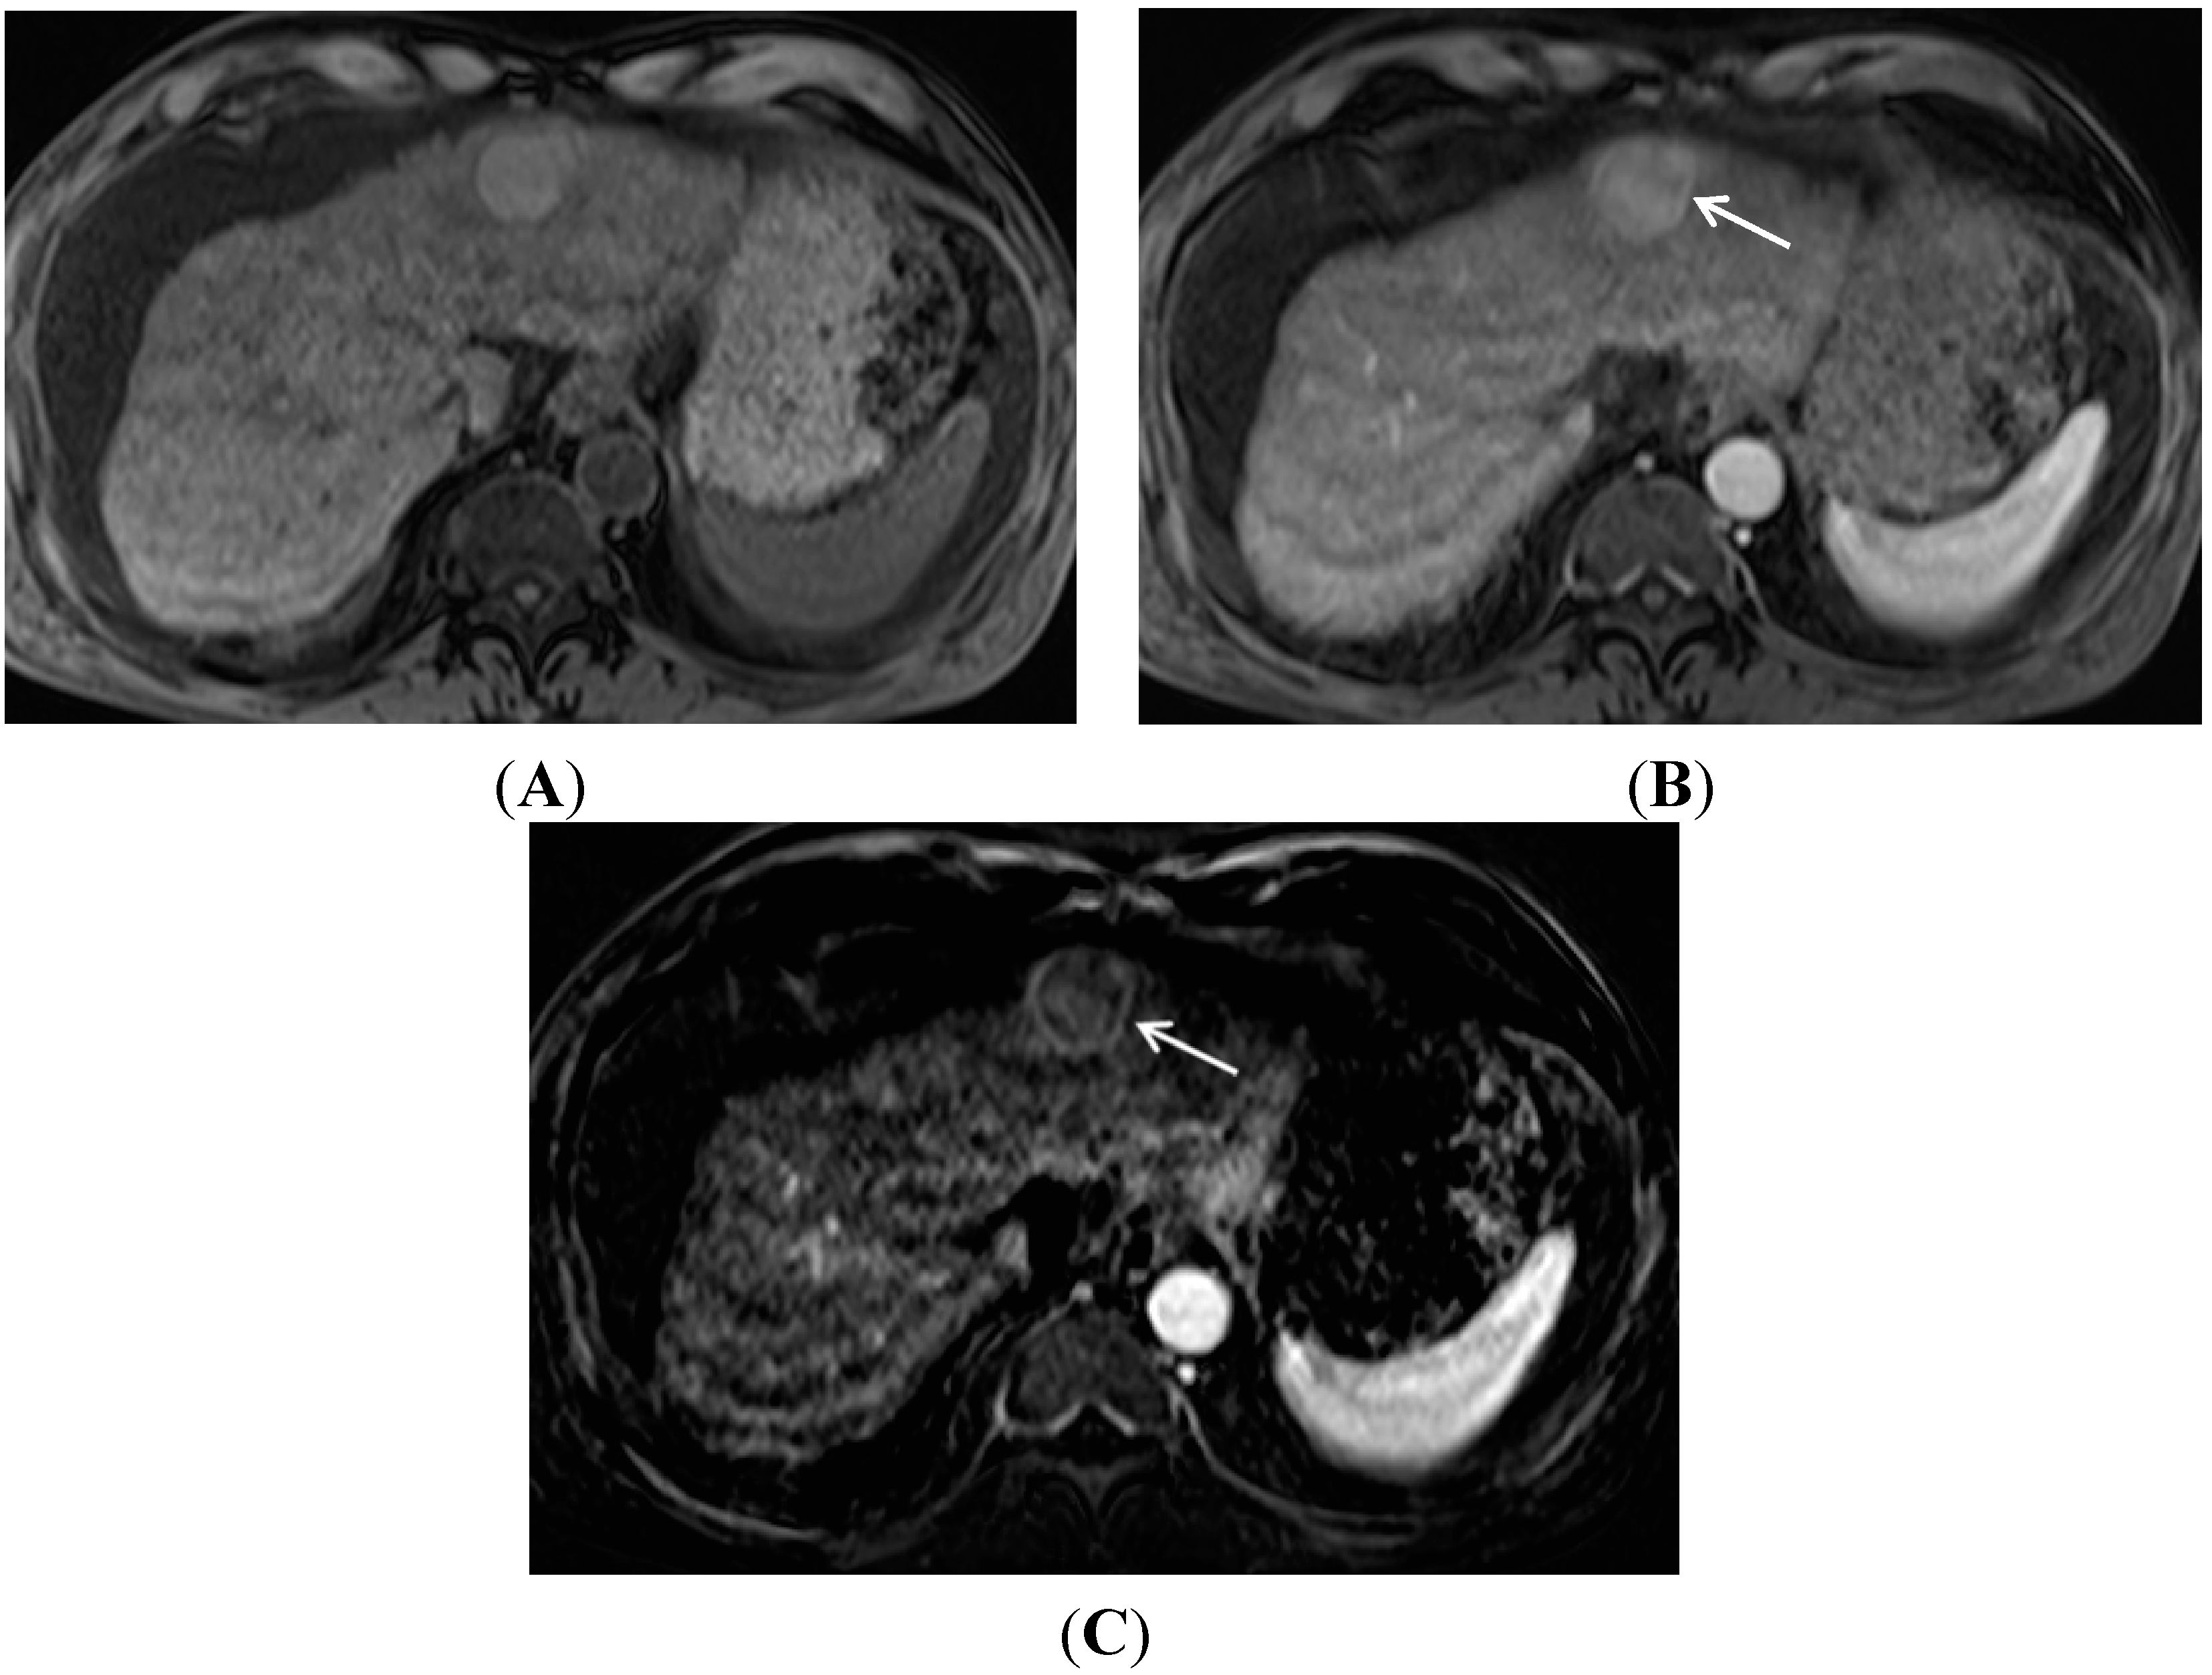

- Lee, M.H.; Kim, S.H.; Park, M.J.; Park, C.K.; Rhim, H. Gadoxetic acid-enhanced hepatobiliary phase MRI and high-b-value diffusion-weighted imaging to distinguish well-differentiated hepatocellular carcinomas from benign nodules in patients with chronic liver disease. Am. J. Roentgenol. 2011, 197, W868–W875. [Google Scholar] [CrossRef] [PubMed]

- Motosugi, U.; Bannas, P.; Sano, K.; Reeder, S.B. Hepatobiliary MR contrast agents in hypovascular hepatocellular carcinoma. J. Magn. Reson. Imaging 2015, 41, 251–265. [Google Scholar] [CrossRef] [PubMed]

- Kitao, A.; Matsui, O.; Yoneda, N.; Kozaka, K.; Kobayashi, S.; Koda, W.; Gabata, T.; Yamashita, T.; Kaneko, S.; Nakanuma, Y.; et al. Hypervascular hepatocellular carcinoma: Correlation between biologic features and signal intensity on gadoxetic acid-enhanced MR images. Radiology 2012, 265, 780–789. [Google Scholar] [CrossRef] [PubMed]

- Kim, J.Y.; Kim, M.J.; Kim, K.A.; Jeong, H.T.; Park, Y.N. Hyperintense HCC on hepatobiliary phase images of gadoxetic acid-enhanced MRI: Correlation with clinical and pathological features. Eur. J. Radiol. 2012, 81, 3877–3882. [Google Scholar] [CrossRef] [PubMed]

- Kim, J.E.; Kim, S.H.; Lee, S.J.; Rhim, H. Hypervascular hepatocellular carcinoma 1 cm or smaller in patients with chronic liver disease: Characterization with gadoxetic acid-enhanced MRI that includes diffusion-weighted imaging. AJR Am. J. Roentgenol. 2011, 196, W758–W765. [Google Scholar] [CrossRef] [PubMed]

- Park, M.J.; Kim, Y.K.; Lee, M.W.; Lee, W.J.; Kim, Y.S.; Kim, S.H.; Choi, D.; Rhim, H. Small hepatocellular carcinomas: Improved sensitivity by combining gadoxetic acid-enhanced and diffusion-weighted mr imaging patterns. Radiology 2012, 264, 761–770. [Google Scholar] [CrossRef] [PubMed]